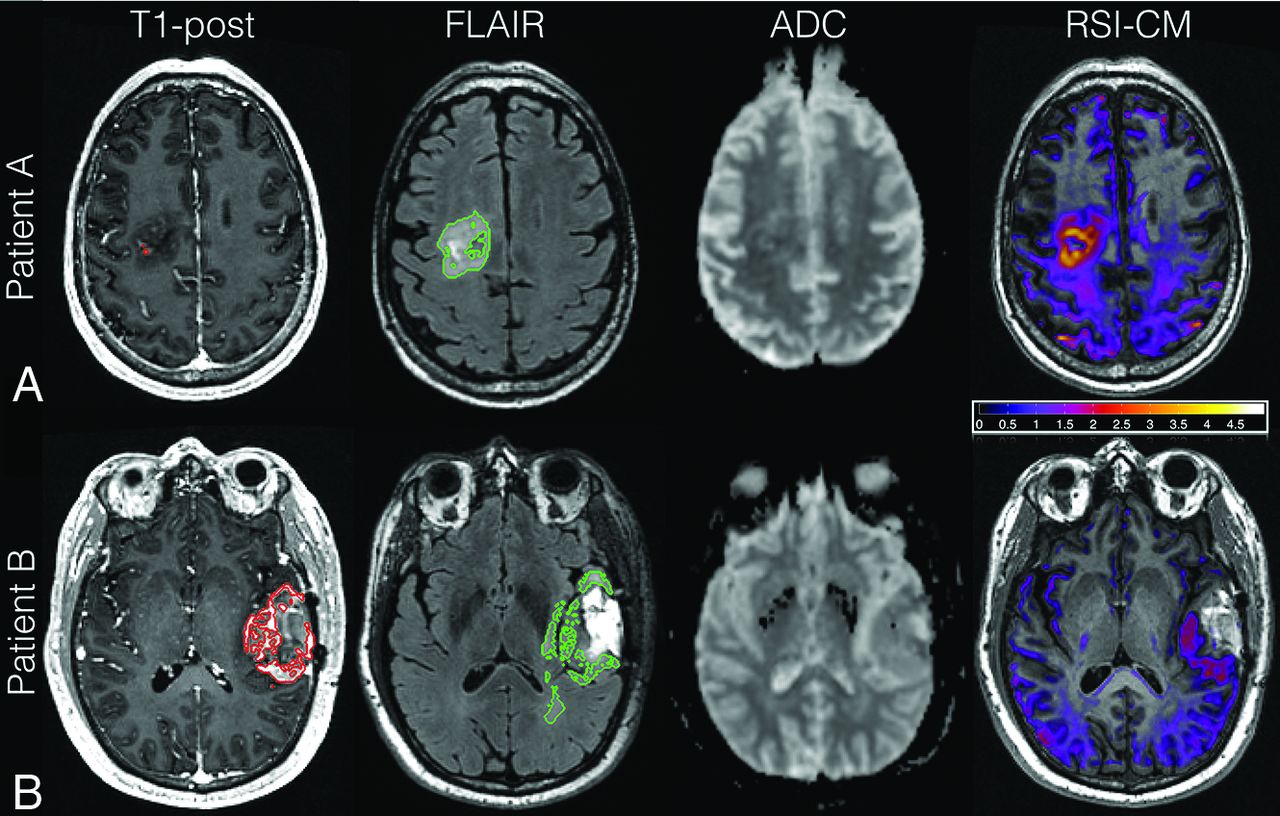

Representative images of 2 patients in this cohort with short (patient A) and long (patient B) PFS are shown in Fig 3. Patient A had lower CEvol, FLAIRvol, and ADC-FLAIR10% but higher RSI-FLAIR90%, RSI-FLAIRvf, and ADC-FLAIRvf than patient B, likely reflecting higher tumor cellularity in the patient's FLAIR-HI region. RSI-cellularity maps exhibited greater conspicuity in this region compared with ADC maps. Accordingly, patient A had shorter PFS and OS compared with patient B.

Shown here are the axial T1-postcontrast, FLAIR, ADC, and RSI-cellularity z score maps acquired postsurgery but pre-RT for 2 patients, A and B. The VOI contours are shown in red and green for the CE and FLAIR-HI, respectively. Patient A is a 63-year-old man with a right posterior frontal GBM who underwent subtotal resection. This patient had high RSI cellularity in the FLAIR-HI region. Although there is corresponding ADC hypointensity in this region, it is subtle and inconspicuous. He had a shorter PFS and OS (PFS, 4.2 months; OS, 6.6 months) than patient B. Patient B is a 31-year-old woman with a right frontal GBM. There are no areas of high RSI cellularity or low ADC signal in the FLAIR-HI or CE region. She had a correspondingly longer PFS (PFS, 14.5 months; OS, 19.9 months).